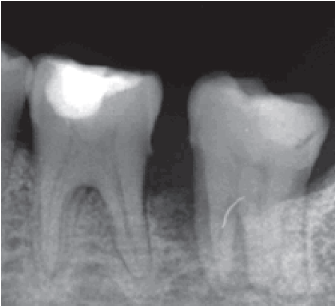

Clínicamente, aparecen como una neoformación vegetante habitualmente sintomática, que deforma el contorno del hueso afectado, y provoca una mucosa eritematosa. La palpación puede ser dolorosa. Una manifestación temprana es el espacio de ligamento periodontal ensanchado, conocido como signo de Garrington (figura 1) [5].

Clínicamente, se evidenciaba una deformidad en el contorno de la región del ángulo mandibular izquierdo. Intraoralmente, se observaba una lesión tumoral de 2,5 cm de alto por 2,7 cm de diámetro. Tomográficamente, estaba registrada una imagen hipodensa en la zona del segundo molar inferior izquierdo, con una expansión de cortical a vestibular y lingual ipsilateral (figuras 2 y 3). Radiográficamente, en la zona periapical del segundo molar inferior izquierdo, se observó un ensanchamiento del espacio del ligamento periodontal, sin causa aparente, con pérdida ósea perirradicular (figura 1). La paciente refirió que un año atrás, aproximadamente, se le había realizado una exodoncia del tercer molar inferior izquierdo, sin complicaciones, concomitante con el crecimiento de dicha lesión. Posterior a la evaluación, los servicios de Cirugía Plástica, Maxilofacial, Cabeza y Cuello realizaron una junta médica, donde se tomó la decisión de llevar a cabo una mandibulectomía segmentaria con reconstrucción de colgajo microvascularizado de cresta iliaca y vaciamiento ganglionar cervical ipsilateral.

La paciente del caso reportado también presentó un rápido crecimiento exofítico de tejido blando, con una superficie eritematosa que implicaba la mucosa alveolar en la zona de los dientes posteriores en el maxilar inferior del lado izquierdo. Esta aparentaba una lesión benigna reactiva común; sin embargo, presentaba características patognomónicas, como el ensanchamiento del espacio del ligamento periodontal y la pérdida de hueso alveolar interproximal y perirradicular, que implicaba el primer y segundo molar inferior izquierdo [9].